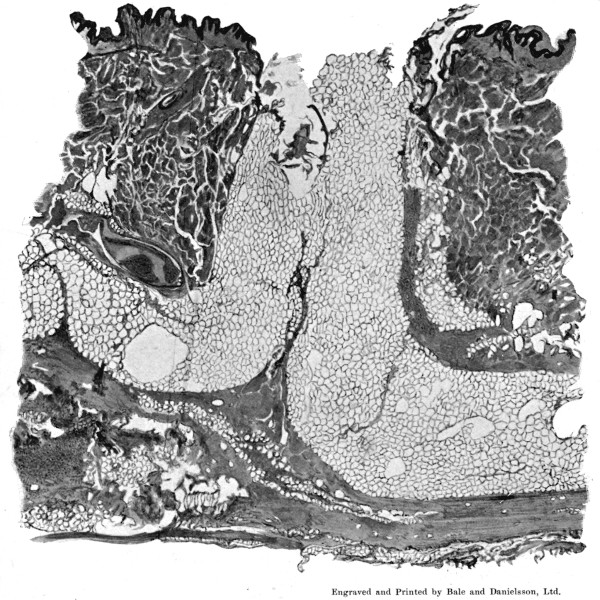

1. Section of Mauser Aperture of Entry To face p. 73

2. Section of Mauser Aperture of Exit 76

25a. Sections of Mauser Entry and Exit Wounds74